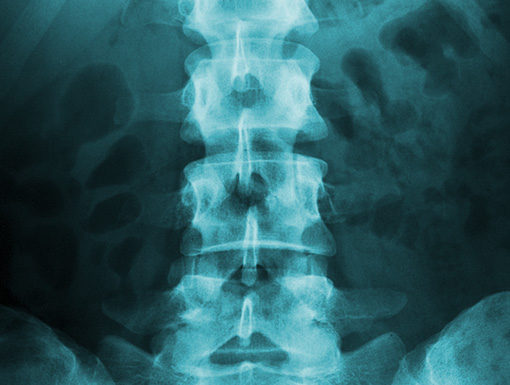

The discs of the spine may deteriorate, bulge or herniate. A disc herniation can occur in any disc of the spine, but the most common occur in the lumbar region. Symptoms of a herniated disc can vary depending on the location of the herniation and type of tissue involved.

If you are interested in learning about the spine and various spine conditions review this interactive spine image.